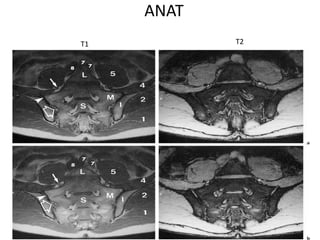

ANAT

T1 T2

1 = Gluteus maximus

2 = Gluteus medius

3 = Gluteus minimus

4 = Iliacus

5 = Psoas

6 = Piriformis

7 = Common iliac artery

8 = Common iliac vein

9 = Inferior gluteal artery and vein

C = Coccyx

I = Ilium

L = L5 vertebral body

M = Sacral lateral mass

S = Sacrum with four sacral elements

and four neural foramina with

visualization of the nerve roots S1–S4